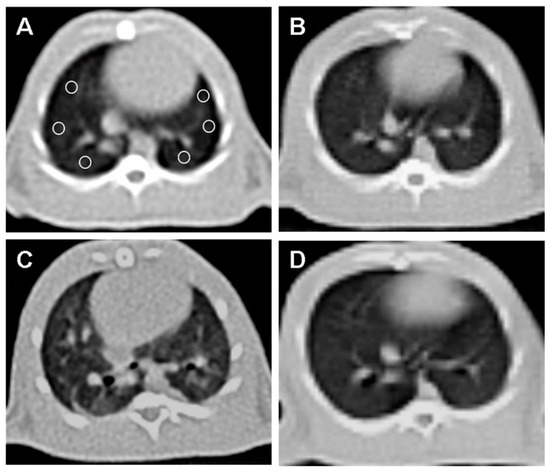

3.4. Computed Tomography (CT) Analysis

| CT [Hounsfield unit (HU) values] | 618.5 ± 9.5 | 465.1 ± 8.8 * p < 0.0001 | 594.2 ± 10.7 # p < 0.001 |